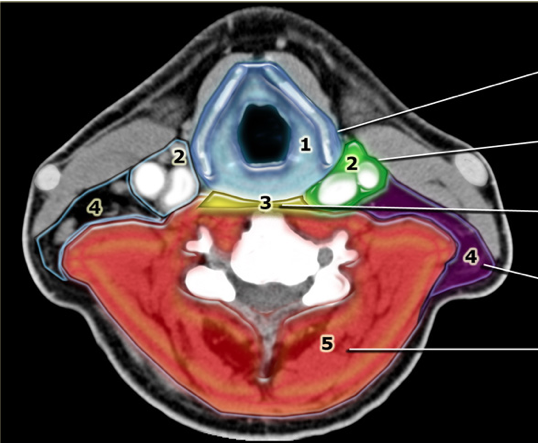

What are the contents of the carotid sheath?